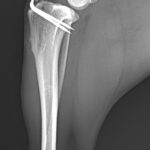

前十字靭帯部分断裂に対するLSS(ラテラルスーチャー法)

小型犬の前十字靭帯部分断裂にラテラルスーチャー法(以下LSS)を実施した。以前、膝蓋骨内方脱臼により大腿骨滑車造溝術、脛骨粗面移行術を行っている。今回、後肢に違和感があるとのことで早急に来院された。幸い完全断裂ではなく部分断裂のようである。大腿骨遠位にチタン製スパイクワッシャー とスクリューによりアンカーを作成、脛骨近位にボーンホールを形成し人工靭帯で締結した。小型犬では症状、年齢、ライフスタイルなどに合わせてLSSによる膝関節安定化術も治療オプションの一つである。